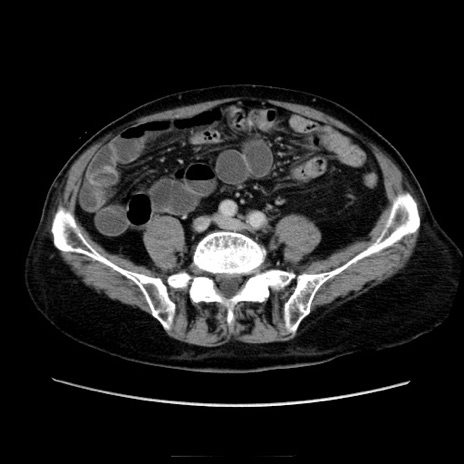

冠状断像

【症例】70歳代男性

【主訴】腹痛

【現病歴】肝硬変・肝細胞癌にてかかりつけの方。約9時間前に食後より腹痛出現。症状が徐々に増悪し、嘔吐出現したため来院。

【既往歴】肝硬変、肝細胞癌(RFA、TACE後)

【身体所見】意識清明、表情苦悶様、BT 36℃、BP 129/78mmHg、P 88bpm、SpO2 97%(RA)、右上腹部から心窩部にかけて圧痛あり、反跳痛なし、筋性防御あり。

【データ】WBC 5800、CRP 0.16